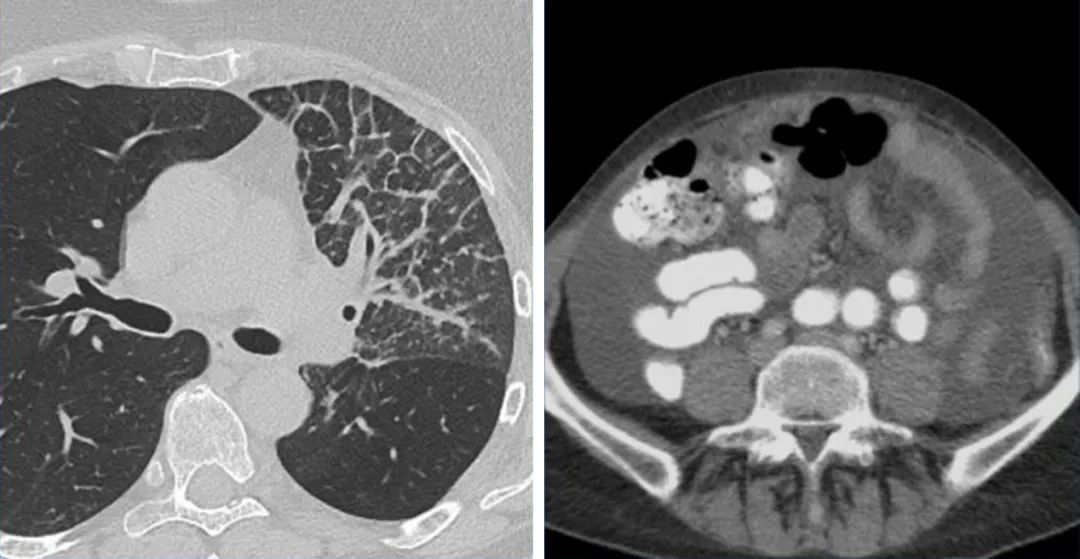

癌性淋巴管炎(左)和腹水(右)均属于不可测量病变,一般记录为非靶病灶,并在后续访视中判断是否存在或消失。

一名34岁女性患有卵巢癌粟粒性肺转移,胸部CT肺窗的MIP图像显示肺内多发转移瘤,

但病灶都太小不能选作靶病灶,可以记录为一个非靶病灶组来评估。